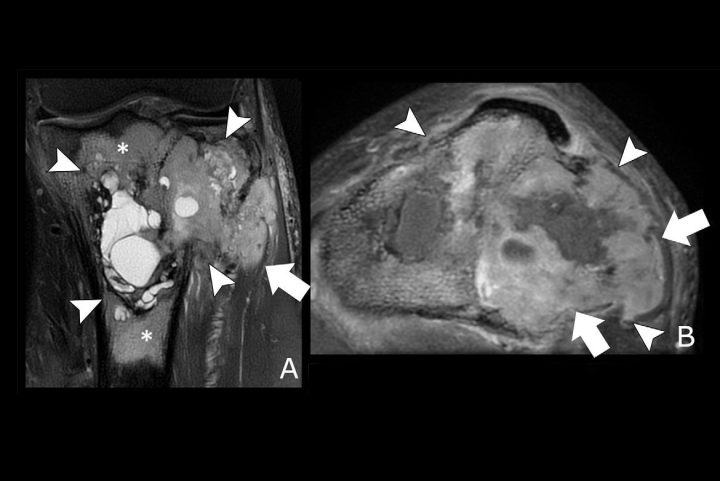

Machine learning standardizes bone tumor grading on MR, CT imaging April 22, 2025 By admin An AI algorithm and an updated risk stratification system produce accurate and standardized bone lesion assessment on CT and MRI.